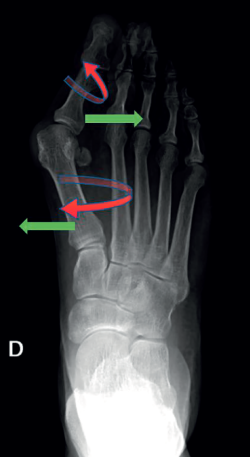

Consiste en una alteración de la articulación metatarsofalángica (MTF) del primer radio del pie. Es una deformidad compleja que incluye, por un lado, la desviación del primer dedo del pie (hallux o dedo gordo) hacia el resto del pie, alejándolo de la línea media del cuerpo (abducto), con una rotación en el plano frontal (pronación del primer dedo). Por otro lado, también incluye la desviación del primer metatarsiano (M1), aproximándolo a la línea media del cuerpo (varo de M1), con una pequeña rotación externa, como se puede ver en la Figura 1. Esta modificación de la articulación afecta a todas las estructuras anatómicas próximas, como la cápsula articular, los ligamentos colaterales, los huesos sesamoideos, la musculatura intrínseca y la extrínseca)(2).

Para realizar una correcta evaluación radiológica se deben realizar al menos 2 proyecciones en carga, una proyección dorsoplantar y una lateral del pie (Figura 2).